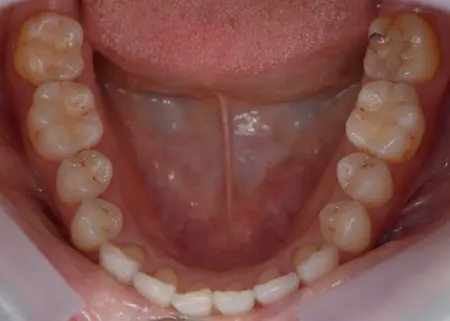

治療前

治療後

拝見したところ、歯が正常な位置からずれたりねじれたりしてデコボコに生えている「叢生(そうせい)」が認められました。

右下奥歯には、他院で治療途中になっていた仮歯が装着されていました。

患者様の場合は、仮歯によって噛み合わせのバランスが崩れて顎関節に負担がかかり、顎の痛みや口が開きにくくなる「顎関節症」を発症していました。

さらに、仮歯以外にも詰め物や被せ物が装着されている歯がありましたが、他の歯とうまく噛み合っておらず、噛み合わせを悪化させていました。

以上のことから、歯並びを整え、仮歯やすでに装着されている詰め物や被せ物を作り直す必要があると診断しました。

まず、上下の歯の表面に「ブラケット」と呼ばれるボタン状の装置を接着し、そこにワイヤーを通して少しずつ歯を動かし、歯並びや噛み合わせを整える矯正治療を行います。

その後、右下奥歯の仮歯を外して新しくブリッジを作製し、装着しました。

最後に、その他の噛み合わせを悪くしている詰め物や被せ物を外して新しく作り直して装着し、噛み合わせに問題がないことを確認して、治療を終了しています。